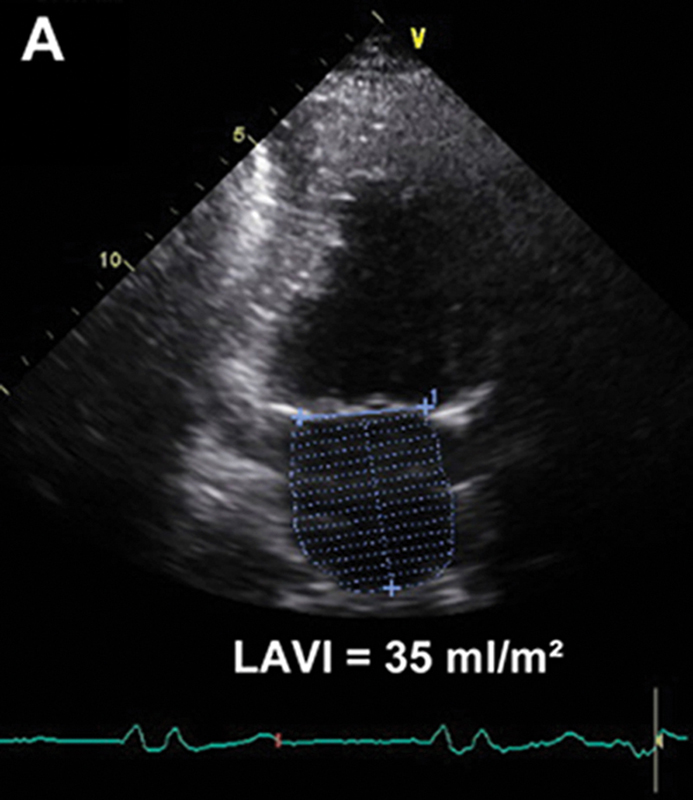

فحوصات تشخيصية لبعض امراض القلب والشرايين التاجية